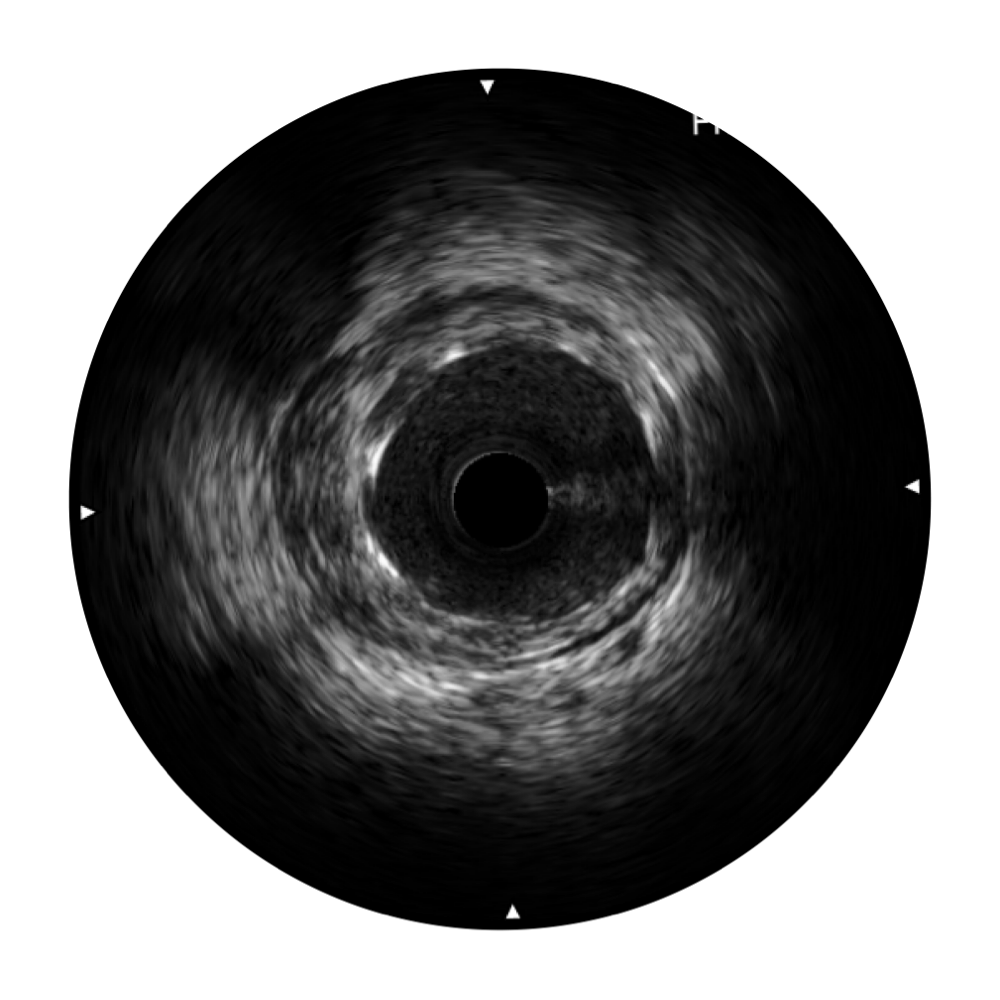

血管内超声(IVUS) 通过对病变程度、性质和累及范围的精确判断,可帮助选择治疗策略和方法,指导介入治疗过程,能够降低主要不良心血管事件,改善预后,在复杂病变介入治疗中用于指导支架置入的优势更为明显。血管内超声(IVUS)已成为精准心血管介入治疗的“金标准”。

宽频成像,兼具高分辨力和更大穿透深度

太阳成tyc7111cc官网超宽频成像技术覆盖20-80MHz1或20-90MHz2频率范围, 提供优异的分辨力同时也保证充足的穿透深度